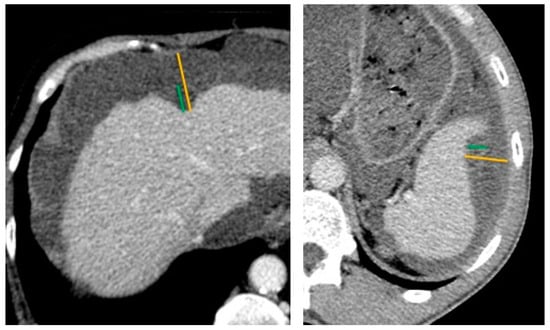

2.2. Preoperative CT-Scan Protocol and Image Analysis

| Scal (Any Kind) Y vs. N | Scal H + S vs. No Scal | Scal H > 20 mm | Scal S > 10 mm | |

| Se | 75% | 55% | 53% | 91% |

| Sp | 61% | 73% | 88% | 28% |

| PPV | 26% | 28% | 62% | 32% |

| NPV | 93% | 90% | 84% | 89% |

| Histologic grade (low vs. high) | ||||

| Se | 58% | 42% | 39% | 8% |

| Sp | 57% | 72% | 93% | 89% |

| PPV | 38% | 41% | 78% | 33% |

| NPV | 75% | 73% | 71% | 59% |

| Liver scalloping 1 | ||||||||

| max depth (mm) | 11.0 [7.0, 17.0] | 21.0 [11.5, 24.0] | 71 (55%) | 0.007 | 11.0 [7.0, 17.0] | 13.5 [10.0, 24.5] | 52 (53%) | 0.2 |

| max depth Hotta (mm) | 14.0 [8.5, 27.0] | 23.0 [18.0, 32.5] | 71 (55%) | 0.038 | 14.0 [7.0, 26.0] | 15.5 [10.8, 25.0] | 52 (53%) | 0.4 |

| Splenic scalloping 1 | ||||||||

| max depth (mm) | 10.0 [8.0, 12.0] | 12.0 [10.0, 15.0] | 89 (69%) | 0.3 | 12.0 [10.0, 13.5] | 9.0 [7.0, 10.0] | 67 (68%) | 0.014 |